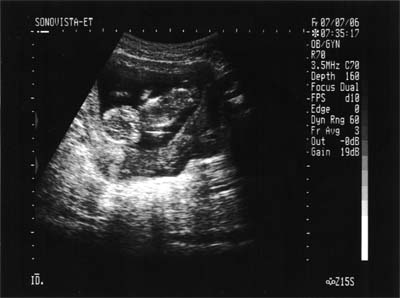

| 2006年7月7日(金) |

| 13w5d 4ヶ月検診を兼ねた助産師外来 寝てるようであまり動いてくれなくて心配したけど、 上げてた手(1枚目)を下に下げて(2枚目)動いてくれました。 助産師さんだったからか、大きさは測ってくれなかったのでわかりません。 |